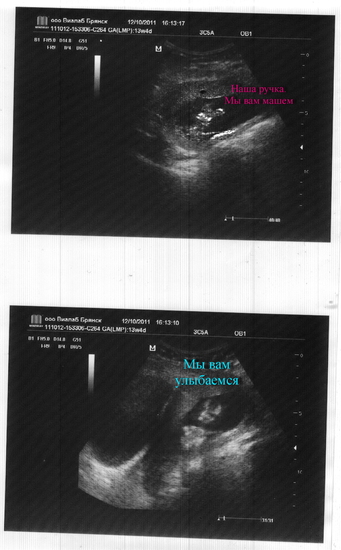

Двойное узи

Поликлинника, приём 5 минут, даже не показали...только вид сбоку остаточный-голова да пузико... Результаты ниже.

20 минут бережного рассматривания, показали мне и ручки, и ножки. Стали показывать личико, а он пальчики на ладошках растопырили прикрыл всё до глаз: На мама, считай. Эти десять малюсеньких пальчиков, просто прелесть.Ручками у личика копошиться))) Стали показывать ножки, а он ими сначала подергал, а потом одну на другую положил)Даже 4 фоточки для папы сделали, в след. раз с флешкой можно, на видео запишут) Результаты ниже.

Больница:В матке виз-ся 1 плодное яйцо. Желт.меш-к не опред-ся, КТР 53 мм, соотв-т 12,4 нед Б. Сердцебиение плода+, двиг.акт-сть+.Толщина воротникового простр-ва - мм, локализ-я плаценты передняя, правая, боковая стенки, толщина пл-ты 12 мм, стр-ра не изменена. Нормотонус. длина шейки матки 26мм, зев закрыт.

ИНВИТРО: вполости матки виз-ся 1 плод, ктр 59 мм, ссотв-т менстр. сроку Б 13 нед, ЧССП 189 ударов в мин, толщина воротникового пр-ва плода 1 мм, желт. меш-к не виз-ся, локал-я плаценты передняя правая, боковая, толщина 14,5 мм, визуал-я удовлетворит., беременность 13 нед.